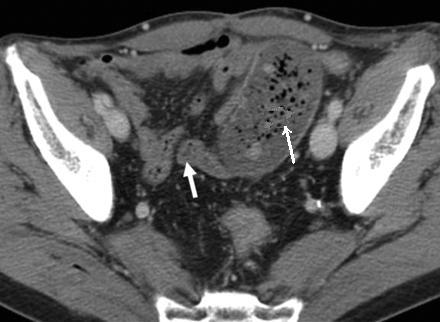

Image TDM en coupe axiale :

Signe de feces' c'est la retention de fesce dans la

portion sus -lesionelle de l'intestin ( fleche

blanche ) . |